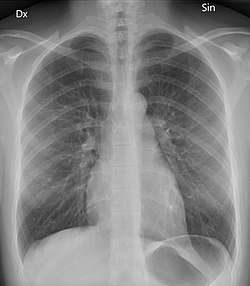

![]() A normal posteroanterior (PA) chest radiograph of someone without any signs of injury. Dx and Sin stand for "right" and "left" respectively. | |